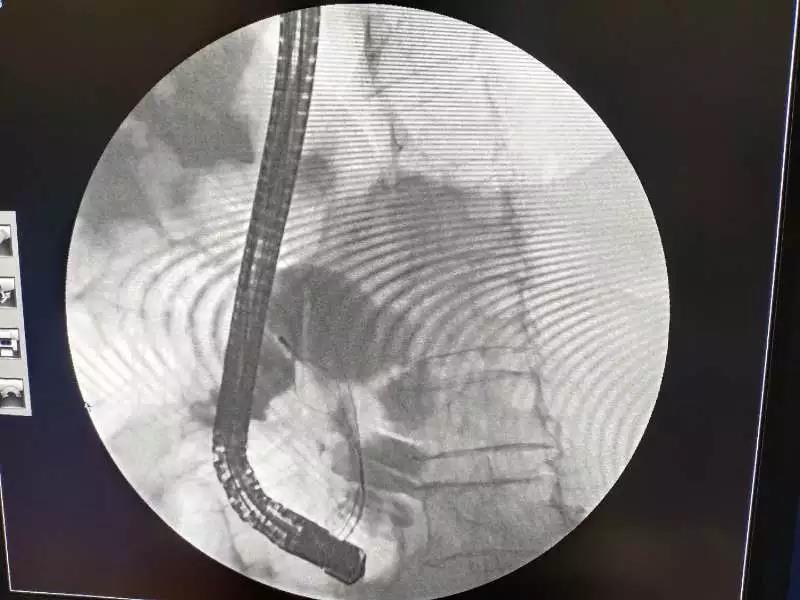

12月18日,我院消化内科主治医师马斌、胃镜室护理人员联合医学影像科顺利为一名胆总管多发结石患者实施了经内镜逆行胰胆管造影术(ERCP)+经内镜奥狄氏括约肌切开取石术(ECT)+经十二指肠镜乳头扩张术+经电子内镜鼻胆管引流术(ENBD)。

(术前影像资料 )

患者,女性,68岁,因“间断上腹部胀痛伴恶心、呕吐10余天”就诊于消化内科。入院后完善上腹部B超检查示:肝外胆管显示段扩张,管腔内所见强回声多考虑为胆管结石(1.7cm×1.1cm),上腹部MRI+MRCP+DWI示:1.胆总管扩张并中下段多发结石2.胆囊大并胆汁淤积3.胰管扩张,消化内科医师团队商议后决定为患者行经内镜逆行性胰胆管造影术(ERCP)进行取石,手术顺利完成,患者安返病房,目前恢复良好。